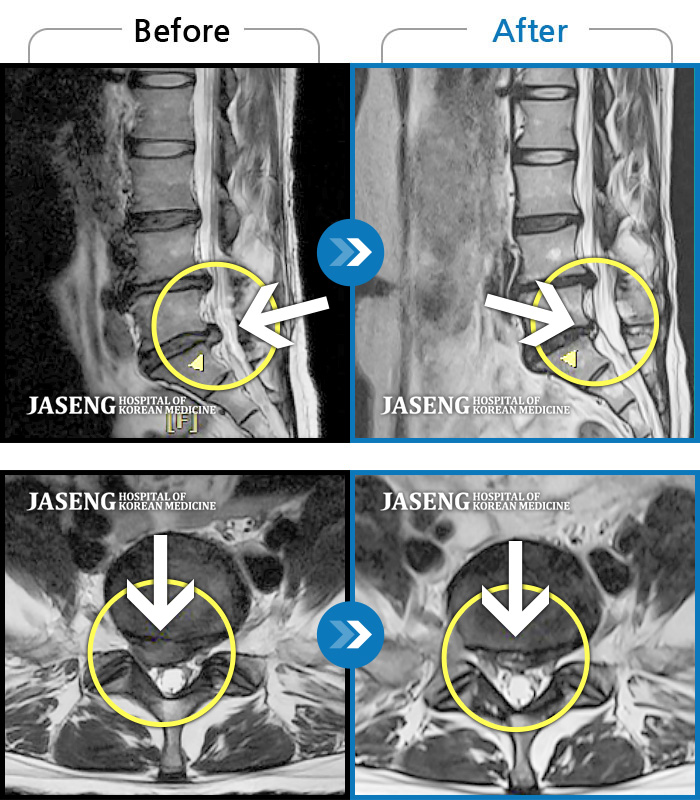

허리디스크

도움받은 사례

광주 · 장영우 원장

좌측 허리 통증으로 허리를 반듯이 펴고 서있기 힘들어 내원하셨습니다.

촬영시기

2024.08.12 ~ 2025.02.26

2025.03.07

조회수 451